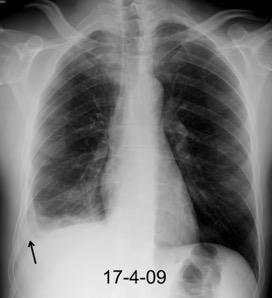

Neumonía a neumococos base izda. con derrame que aumenta.

Broncograma en lateral y en US.

(36-66% en ingresados)

66 pacientes con

Tb pleural probada

Ocasionalmente nivel hidro-aéreo por fístula broncopleural Consolidación........3% Ganglios……….....39%

Derrame...................65-98.5%

Lesiones pleurales. ........38 %

Afect. cisura interlobar….9%

Pl. mediastínica........... 1.5%

Afect. pulmonar 26/66 … 39%

Cambios fibróticos..........17%

Cavitación ......................12%

Nódulos heterogéneos.....6%